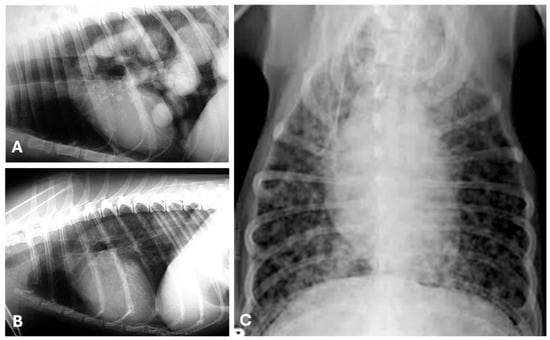

4.1. Radiography

- Otoni, C.C.; Rahal, S.C.; Vulcano, L.C.; Ribeiro, S.M.; Hette, K.; Giordano, T.; Doiche, D.P.; Amorim, R.L. Survey Radiography and Computerized Tomography Imaging of the Thorax in Female Dogs with Mammary Tumors. Acta Vet. Scand. 2010, 52, 20. [Google Scholar] [CrossRef]

- Lekshmi, S.L.; Nair, S.S.; Sajitha, I.S.; Ramankutty, S.; Narayanan, M.K.; John Martin, K.D. Radiographic Assessment of Pulmonary Metastatic Lesions in Superficial Cutaneous and Mammary Neoplasms in Dogs. J. Vet. Anim. Sci. 2021, 52, 393–398. [Google Scholar] [CrossRef]